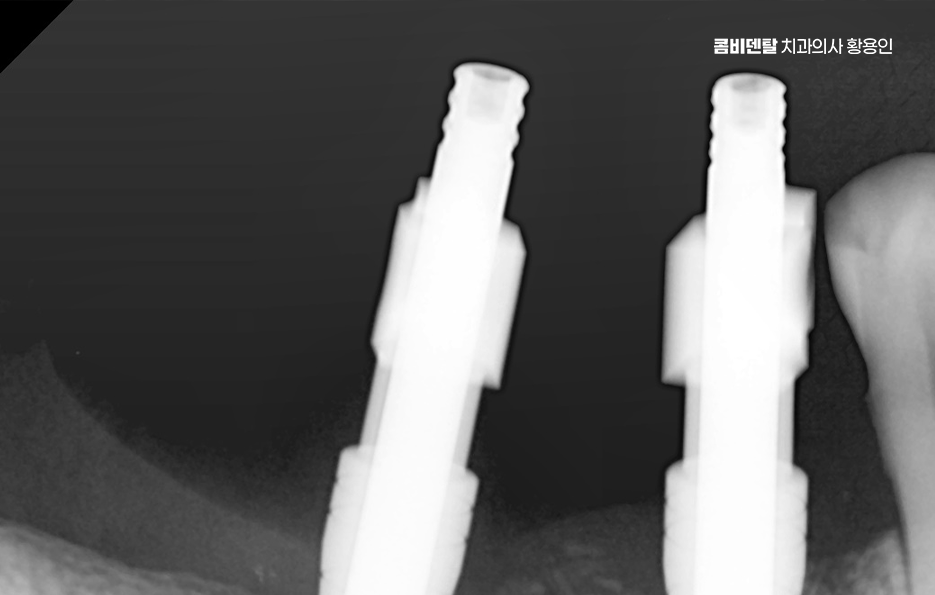

나에게 맞는 치료를 하기 위해서는 정확한 진단과 설계가 중요하며 CT 촬영 등을 통해 신경 위치, 뼈의 양, 두께 등을 정밀하게 진단한 다음, 교합과 치열 구조에 맞는 위치에 임플란트를 심는 게 중요한데 잘못된 위치에 심어지면 오래 쓰기 어렵고, 나중에 통증이나 염증이 생길 수 있었어요.